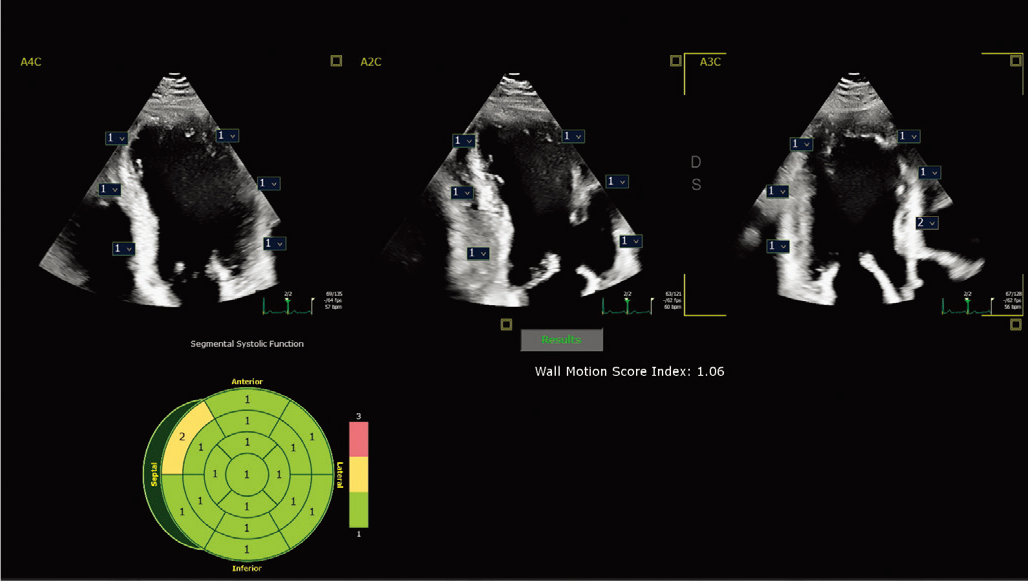

现配备 2D 自动 EF 和中间层应变 Advances 的进步之处在于,它能够在同一应用程序中提供快速、可重复的结果,作为全面 LV 评估的一部分,从而改善工作流程并节省时间。 | ![]() 自动节段性室壁运动评分* 在标准 17 段靶心显示屏上自动评估壁运动,以帮助客观评估 LV 壁。 |

X5-1c 探头进行自动节段性室壁运动评分指数 |